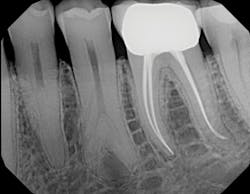

Digital radiograph

I also purchased a DEXIS Platinum Sensor, which is comfortable and sturdy. It is built for reliability and durability, and the image quality is top-notch. As far as usability—from sensor positioning to x-ray capture to documentation—it is all easy to navigate.

My patients now appreciate that I engage them in their own care through the use of technology. I enlarge images on the screen so they can understand their dental condition. The immediate images save time for me and them—patients no longer have to wait for x-rays to be developed (or wait even longer for retakes).